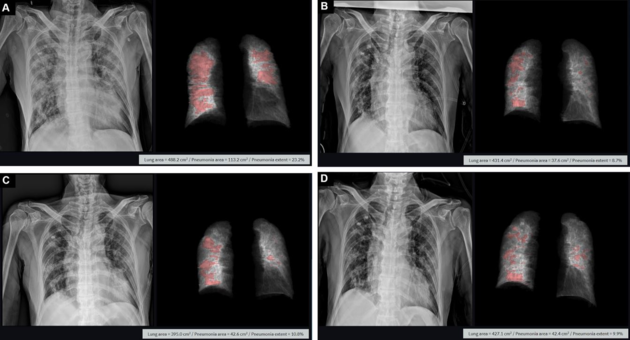

PLOS ONE에 게재된 코로나19 확진자 X-ray 및 티셉 활용 폐렴 분석 화면

티셉은 메디컬아이피의 의료영상 AI 분석 원천기술을 토대로 2차원 X-ray에서 코로나19 폐렴 병변의 크기(cm²), 전체 폐실질에서 병변이 차지하는 비율(%) 등 3차원 정보를 얻을 수 있는 X-ray 정량화 플랫폼이다. 환자의 X-ray에서 폐와 병변을 자동으로 분할하고 수치화 함으로써 객관적 질병 정보를 획득할 수 있는 것은 물론 이를 통해 장기적으로 치료 경과를 확인할 수 있다.